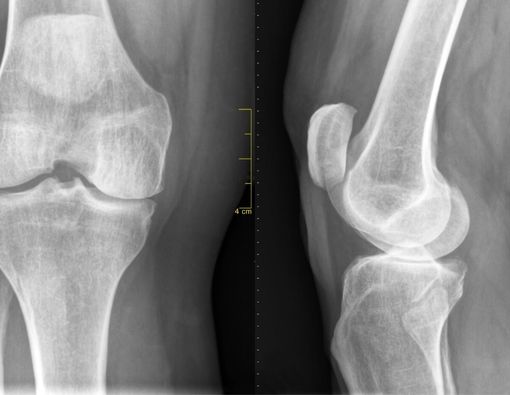

Osteoartritis

Osteoartritis terjadi ketika tulang rawan mengalami penipisan seiring berjalannya waktu. Padahal, tulang rawan berfungsi sebagai bantalan tulang.

Semakin tipis bantalan tulang, semakin besar risiko gesekan yang terjadi. Hal itu dapat menyebabkan kerusakan tulang. Osteoartritis atau radang sendi bisa terjadi di berbagai tempat, namun kondisi ini umum menyerang lutut, pinggul, tulang belakang, dan juga tangan.

Ketika mengalami osteoartritis, tulang akan mengalami pembengkakan dan membuat penderitanya sulit menggerakkan sendi.